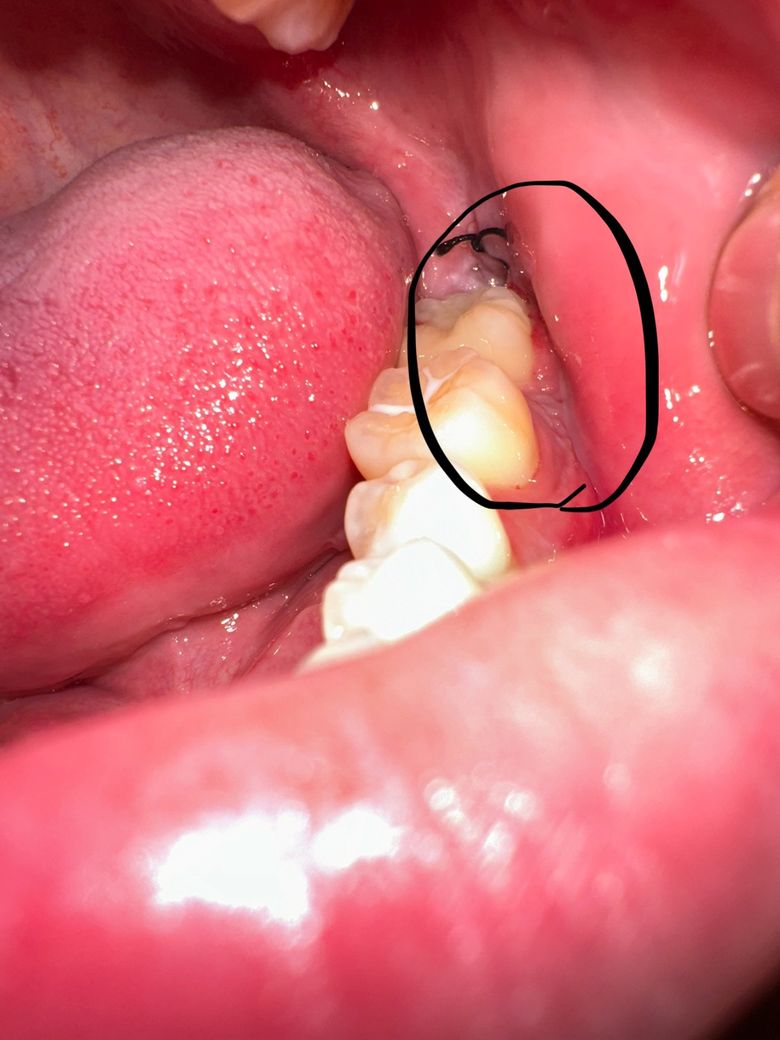

매복사랑니 발치후 잇몸 부음 현상(좀 힘들게 발치했어요)

이번에 왼쪽 아래 발치를 했는데 바로 앞 어금니 잇몸이 부었더라구요 지금 발치한지 4일째 되는데 무슨 문제가 있고 그러진 않겠죠..?

• 1번 째 사진

잇몸절개후 아직 다 아물지 않아서 그러는겁니다. 시간이 지나면 괜찮아 지니 너무 걱정하지마세요.

보통 발치 후 주변 잇몸 부종은 2~3일째까지 나타날 수 있고 점차 호전됩니다. 항생제 약 잘 복용하시기 바랍니다.